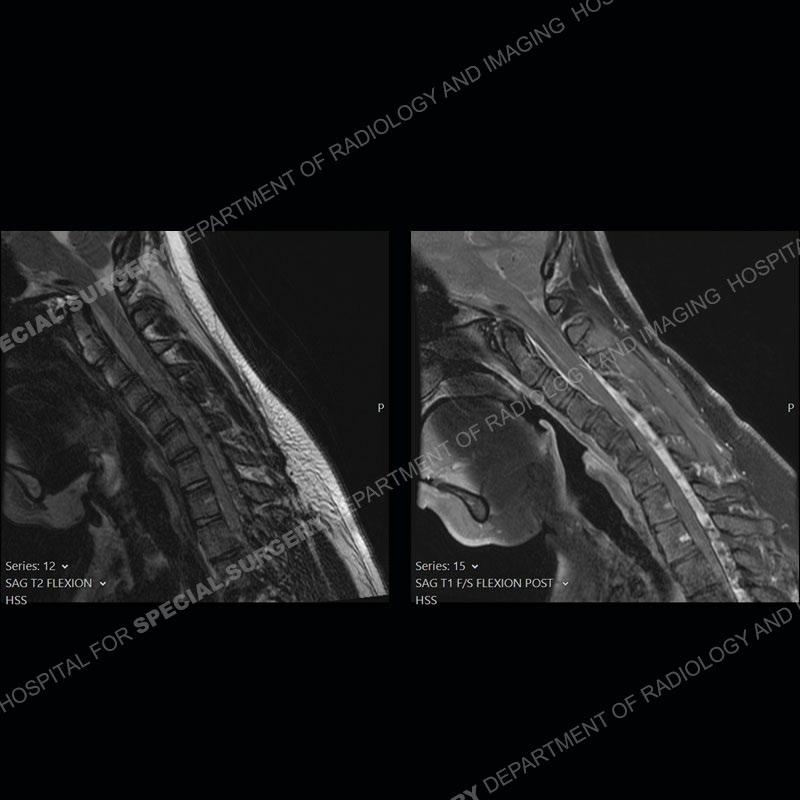

The images on the neutral sagittal images do not demonstrate any appreciable abnormality. On the flexion images, there is a forward displacement of the spinal cord centered on C6-C7. There is an expansion of the posterior dural sac which shows marked enhancement. Prominent flow voids are present of the expanded posterior dural sac on the T2 and T1 post contrast images.

Not present in this case, but frequently found is abnormal T2 signal intensity of the lower cervical cord about the area of maximum forward displacement. This can be seen on the neutral and flexed position imaging. Shown well in this case is the marked, crescentic expansion of the posterior dural sac. The sac shows marked enhancement with prominent flow voids and is often hyperintense on T1 and T2 images. The spinal cord as shown in this case is typically anteriorly displaced about the lower cervical cord.